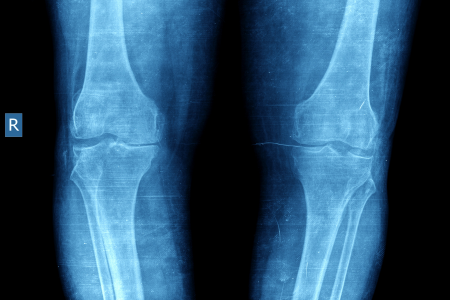

レントゲン検査は、骨の状態を診る検査です。骨はレントゲンをあまり通さないので、レントゲン写真には骨が白く写ります。変形性膝関節症になると、クッションの役割を果たす軟骨がすり減り、骨と骨が直接ぶつかるようになります。すると、骨に負担がかかり、骨の形が変わったり、骨棘(こつきょく:骨のとげのようなもの)と呼ばれる骨のでっぱりができたりします。レントゲン検査では、これらの骨の変化を確認できます。

レントゲン検査では、骨の状態を詳しく知ることができます。具体的には、関節の隙間の狭さや、骨棘の有無などを確認できます。変形性膝関節症が進行すると、関節の隙間が狭くなり、骨棘ができることが多いです。これらの情報は、変形性膝関節症の診断や、病気の進行度合いを判断するのに役立ちます。